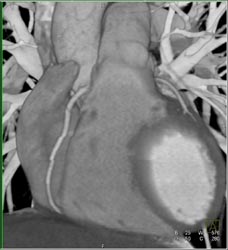

Diagnosis

Normal LAD